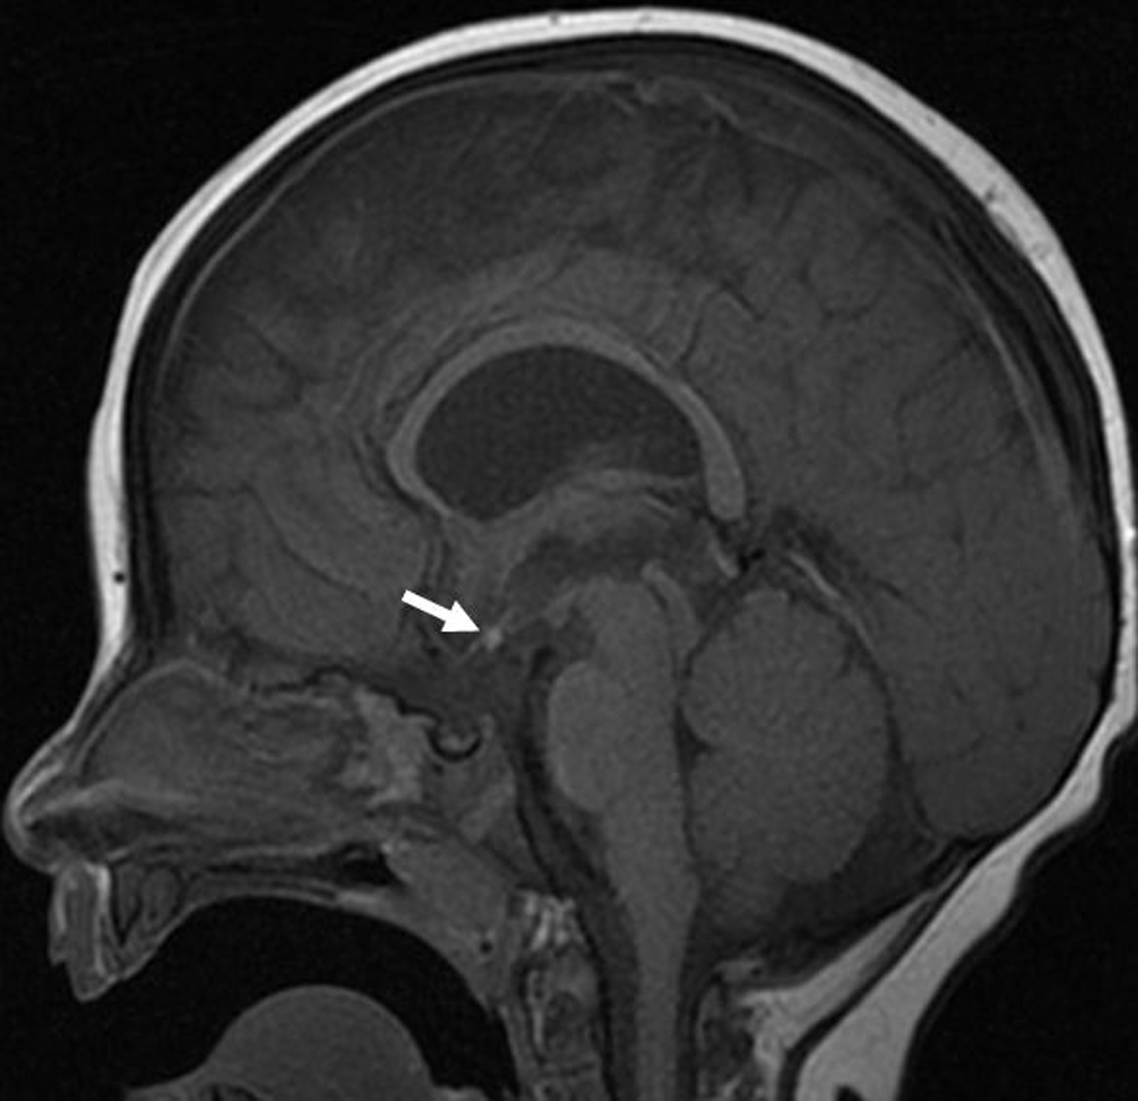

Septo-optic-pituitary dysplasia (SOD) is a neurodevelopmental abnormality that consists of optic nerve(s) hypoplasia (ONH) in association with hypopituitarism and/or midline brain abnormalities (absent septum pellucidum and/or abnormal corpus callosum) (Figures 1 and 2). In addition, neuronal migration disorders (NMD) (Figure 3) have been reported in some patients with SOD. ONH may also occur in isolation. Reference Garcia-Filion and Borchert1,Reference Webb and Dattani2

Figure 2: Sagittal T1-weighted brain MRI image of a 7-month-old male with visual impairment showing an ectopic position of the neurohypophysis. The posterior bright pituitary spot (arrow) is visualized within the hypothalamus region. In addition, the pituitary infundibulum is absent.

There were 128 patients (M = 70) with ONH/SOD who had neuroimaging studies. Their median age (interquartile range) at study end was 12.2 (7.4–17.6) years. Their neuroimaging characteristics and findings are displayed in Table 1. Figures 1 –3 show some of the abnormal neuroimaging features.